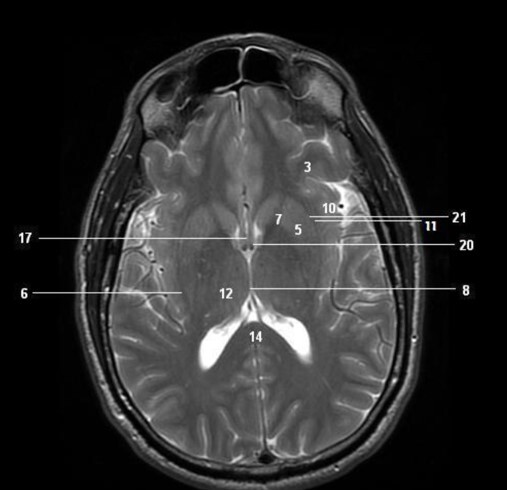

10

Q

Label 1,3,4,5,7

A

1=3rd ventricle

3-Anterior commissure

4=Pineal gland

5=Choroid plexus

7=Posterior commissure

11

Label 4,5,6,8,9

4=Genu, CC

5=Lt lateral ventricle (body)

6=Head of Rt caudate nucleus

8-Rt Lentiform nucleus

9=Lt lateral ventricle (post. horn)